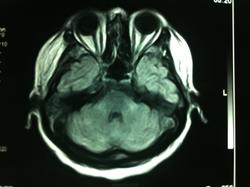

Женщина 48 лет, поступила с подозрением не ОНМК. На КТ -данных за ОНМК не обнаружено, но в правой орбите ретробульбарно мягкотканное образование +45HU, признаков деструкции и ремоделирования костных структур орбиты не наблюдается, медиальная и нижняя прямая мышца отчетливо не дифференцируются, зрительный нерв тесно прилежит к данному образованию. После КУ гомогенное накопление КВ и повышение плотности до +65HU. Экзофтальм. Жалобы на снижение зрения. Год назад делала МРТ ГМ, на снимке патологии орбит не увидел. Идиопатическая псевдоопухоль орбиты?

МРТ 11.08.13